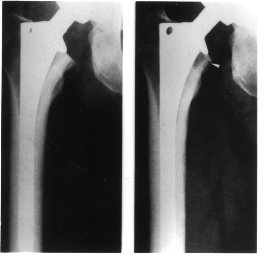

X-rays

Figure 1. X-rays of a femoral prosthesis. Compare the bone a) immediately after surgery and b) after the prosthesis has induced bone loss.